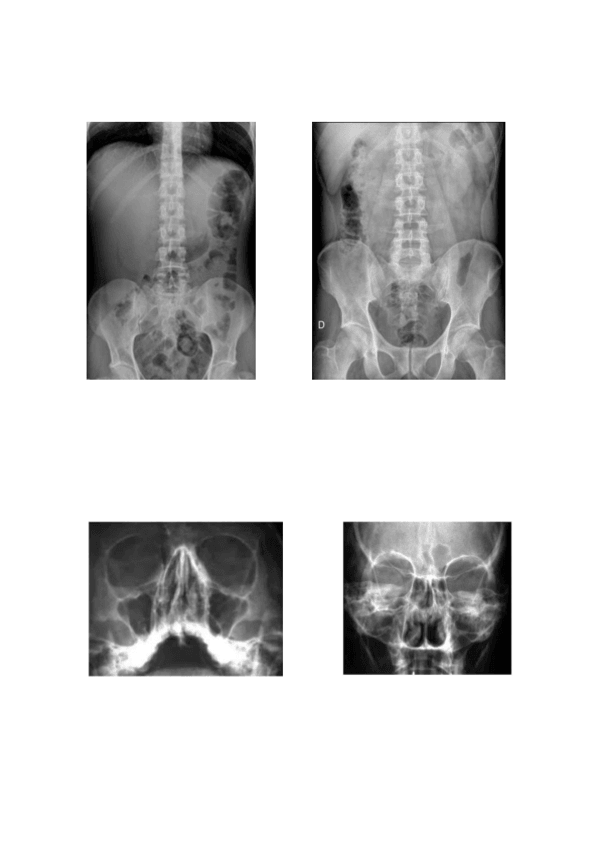

RADIOLOGÍA SIMPLE